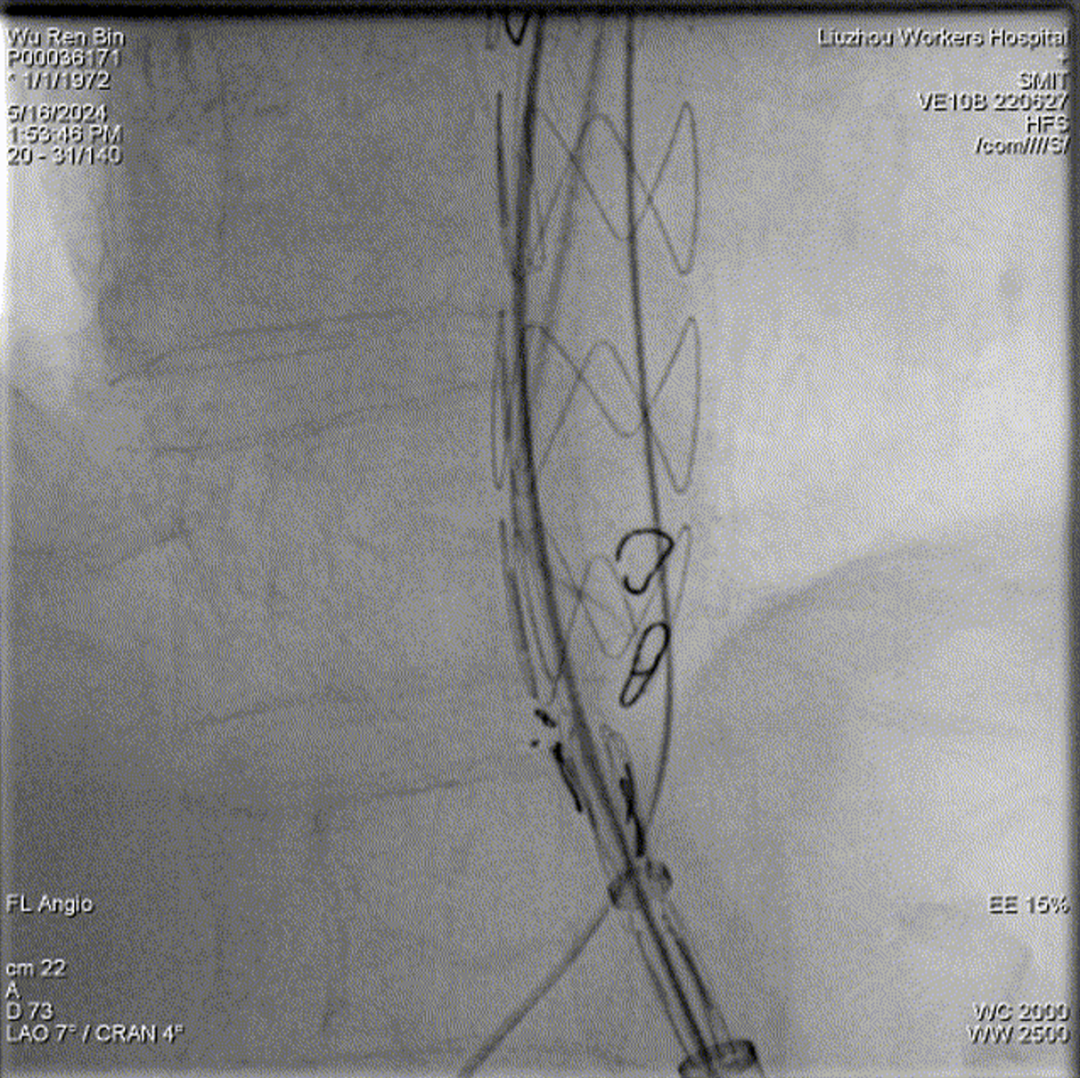

术中3D影像引导,主体支架精准定位

3D影像引导下,

主体支架窗口与弓上三分支开口对位

依次超选无名、左颈总及左锁骨下动脉

术后造影,支架形态良好,分支血流通畅